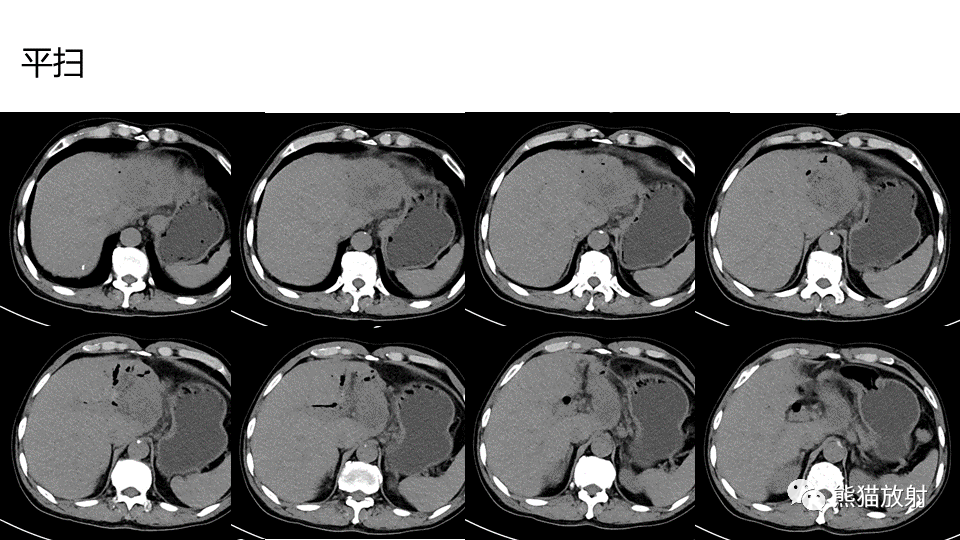

【PPT】肝内胆管细胞癌 VS 肝脓肿

【PPT】肝内胆管细胞癌 VS 肝脓肿-4